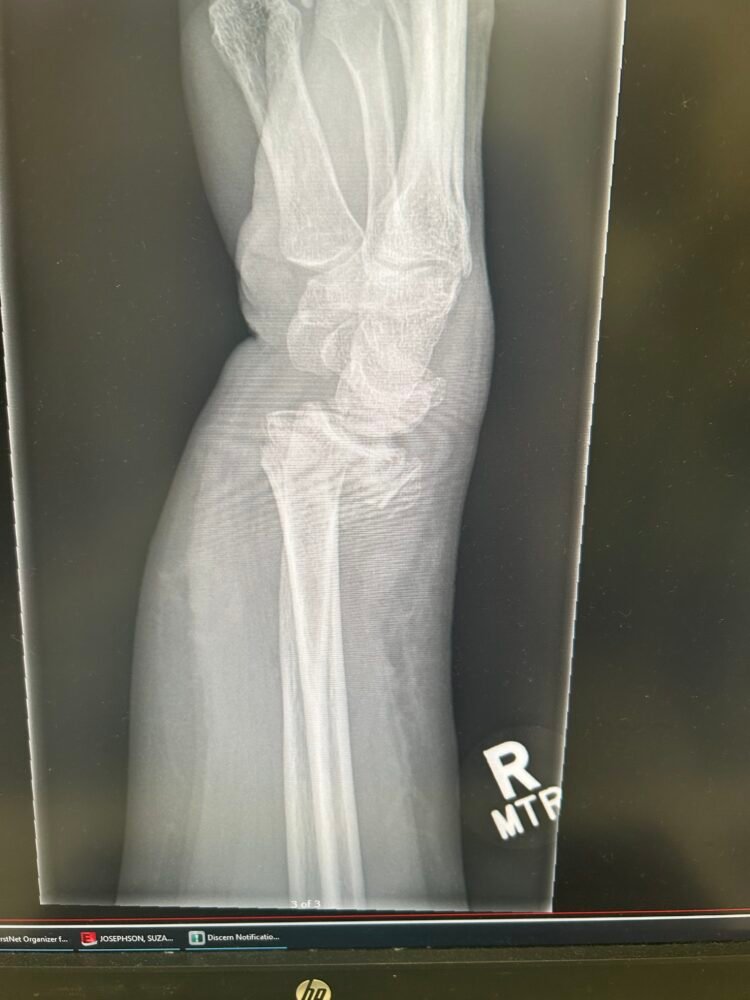

The title of this post mentions a glitch and that would be that I had a fall and broke my wrist quite badly and needed surgery to insert plates . This has meant that I have not been able to do any of the packing up and removal of the kitchen. It is extremely frustrating to say the least.